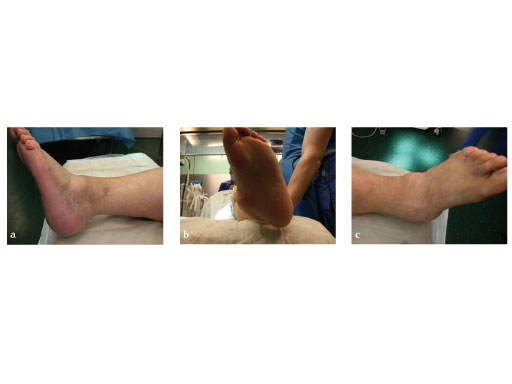

42-year-old, female with severe insulin-dependent diabetes mellitus (IDDM); Charcot foot, wheel chair since 1 year.

Case provided by Hermann Bail, Berlin, DE